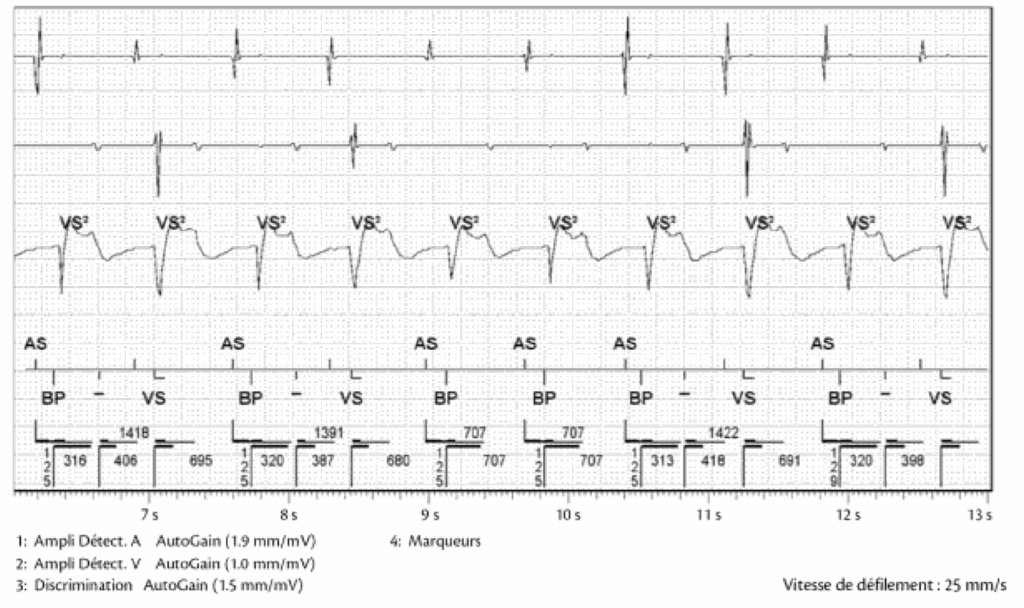

TWOS : T Wave Oversensing